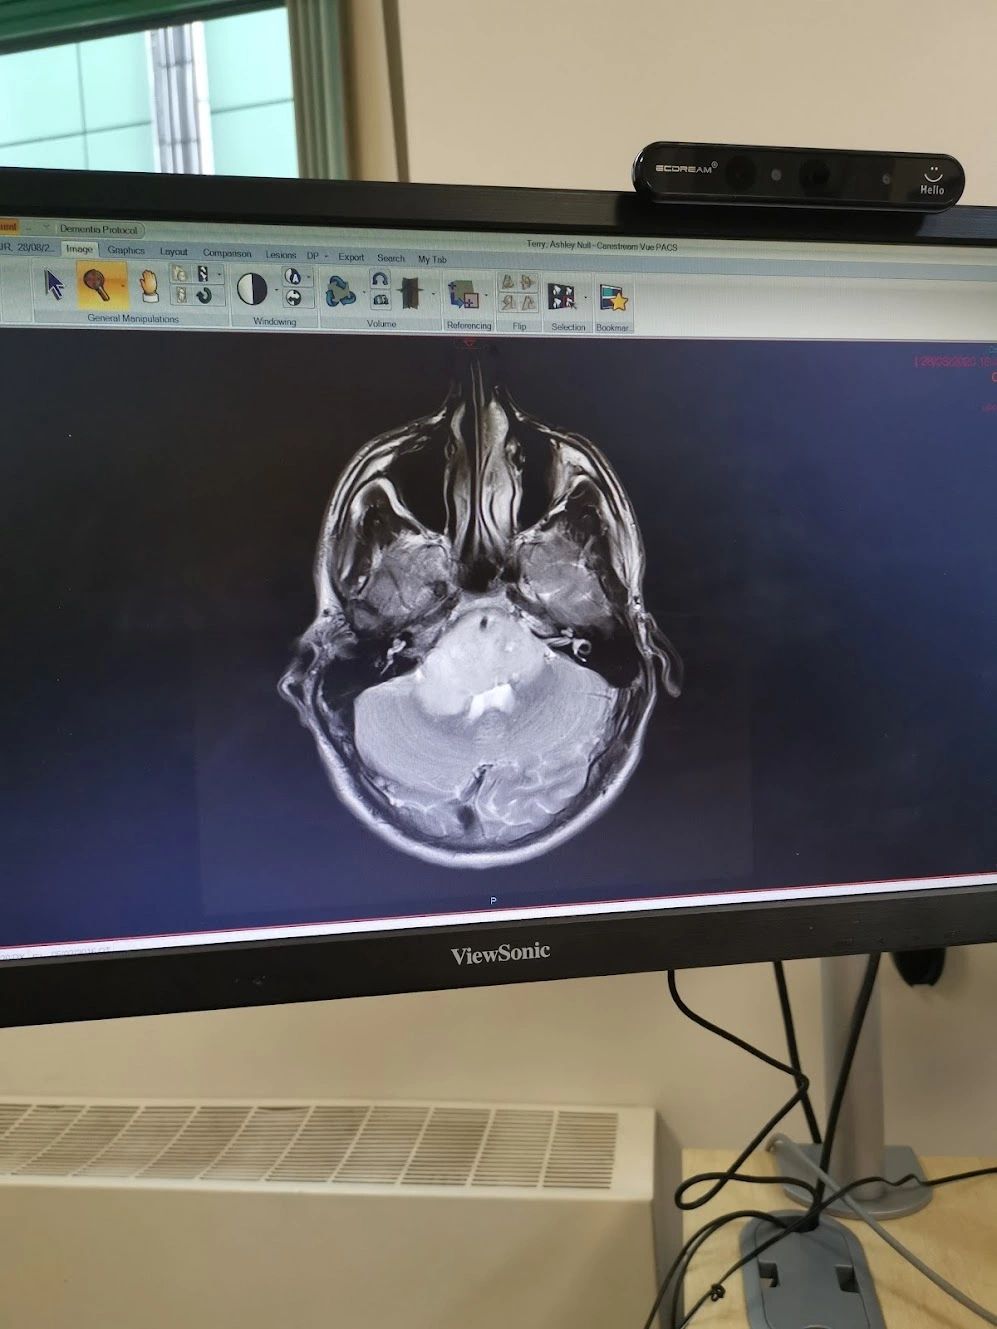

Back in August 2020 I was diagnosed with a tumour in my brain stem, roughly the size of a tennis ball, and was given 6-12 months to live unless I were to undergo intensive treatment to try to stop the tumour from growing or shifting.

After struggling for weeks to see a doctor and get some help, I eventually agreed to go to A&E as by the end of August I was starting to lose movement in my left side. After a long and boring 8 hours sitting around in A&E I was lucky enough to see a doctor who got me straight in for an MRI, which revealed something was seriously not right. I then spent 3 days in my local hospital receiving intensive care without really knowing what was going on, before going into a specialist hospital with more experience of brain tumors. There I met an amazing group of people who were able to give me all the information I was desperately looking for and we discussed my options. This began with me having a brain biopsy (side note: This operation is normally done under local anesthetic, how on earth do people sit for 3-4 hours whilst someone is drilling and digging into your brain? Madness! Hats off to those brave soles). Anyway, I then went onto a third hospital with a dedicated cancer treatment department where I met even more amazing people and this is where I spent the next 15months of my treatment.